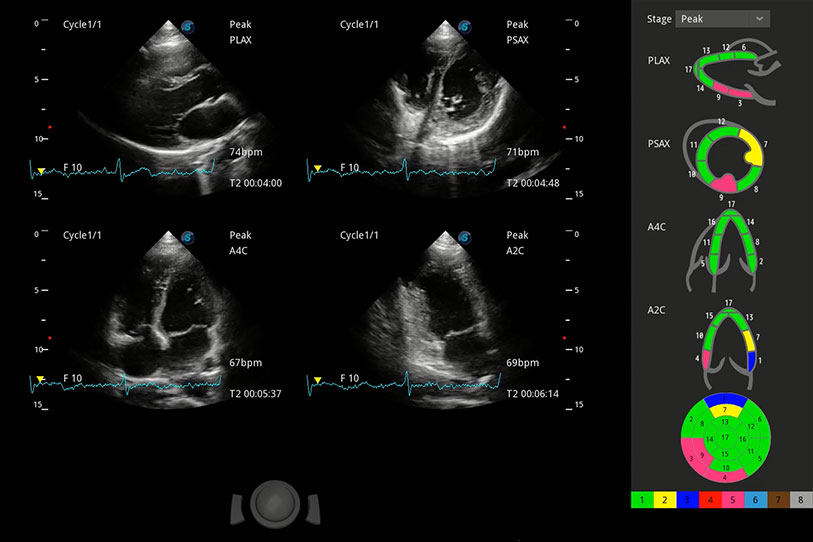

能够基于左心室壁追踪和辛普森法,自动计算射血分数,支持多个可移动点描迹,与手动测量相比,极大节省了动物医生的时间和精力。

具备多种协议可选,同时支持17阶段划分法和专业的SE报告。

通过360度任意调节3条M型取样线,在同一心动周期上观察心脏不同位置的运动曲线,得到准确的心功能测量数据,有效评估心肌运动及左心室功能。

实时用颜色表示心肌组织运动,观察和定量组织的运动情况,对快速检测与评估心肌的灌注和活性、电传导及心肌收缩和舒张功能等均能提供重要的诊断信息。